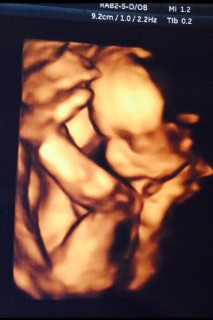

赤ちゃんがママの声を聞こえるようになります。

この頃から赤ちゃんはママの声が聞こえるようになります。おなかの赤ちゃんに語りかけることを胎教(たいきょう)をいいます。赤ちゃんが直接理解するわけではありませんが、ママがリラックスすることが赤ちゃんの発達の刺激になるのです。